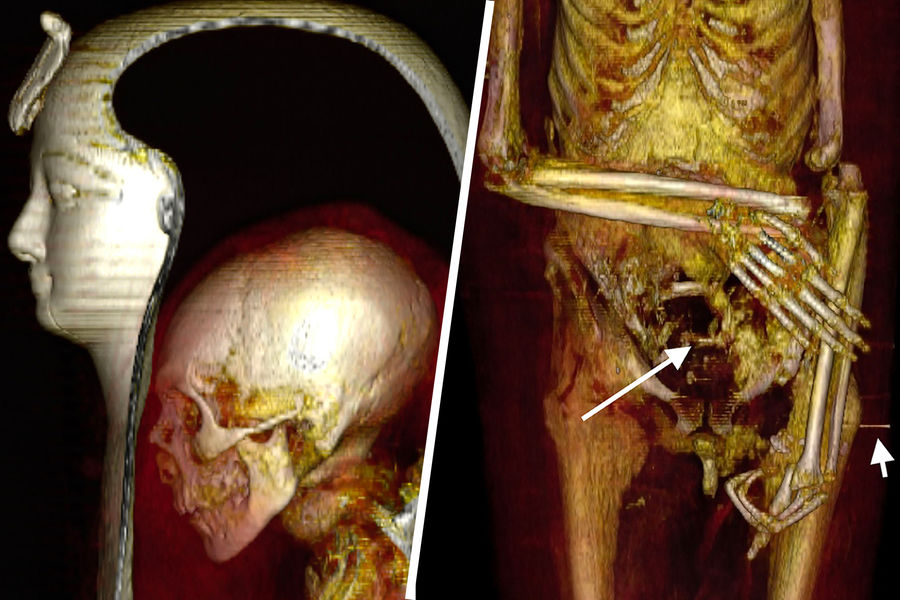

Также КТ позволила лучше рассмотреть лицо мумии — овальное, с впалыми глазами и обвисшими щеками.

Нос маленький, узкий, приплюснутый. Верхние зубы слегка выступают. Подбородок узкий. Уши маленькие, левое проколото. На затылке сохранились несколько вьющихся локонов. Возможно, эти данные можно будет использовать для реконструкции лица фараона.

Мозг перед мумификацией не извлекался — он сохранился в черепе. Сам череп тоже был нетронут. Но внутренние органы были удалены через отверстие в боку, через него же тело было набито тканью. Сердце осталось на месте.

При повторном захоронении мумию явно пытались «отремонтировать» — пропитанные смолой бинты фиксировали оторвавшуюся из-за перелома шейных позвонков голову, прикрывали повреждения брюшной полости. Сломанным и вывихнутым конечностям придано подходящее положение. Ступни зафиксированы с помощью деревянных дощечек.